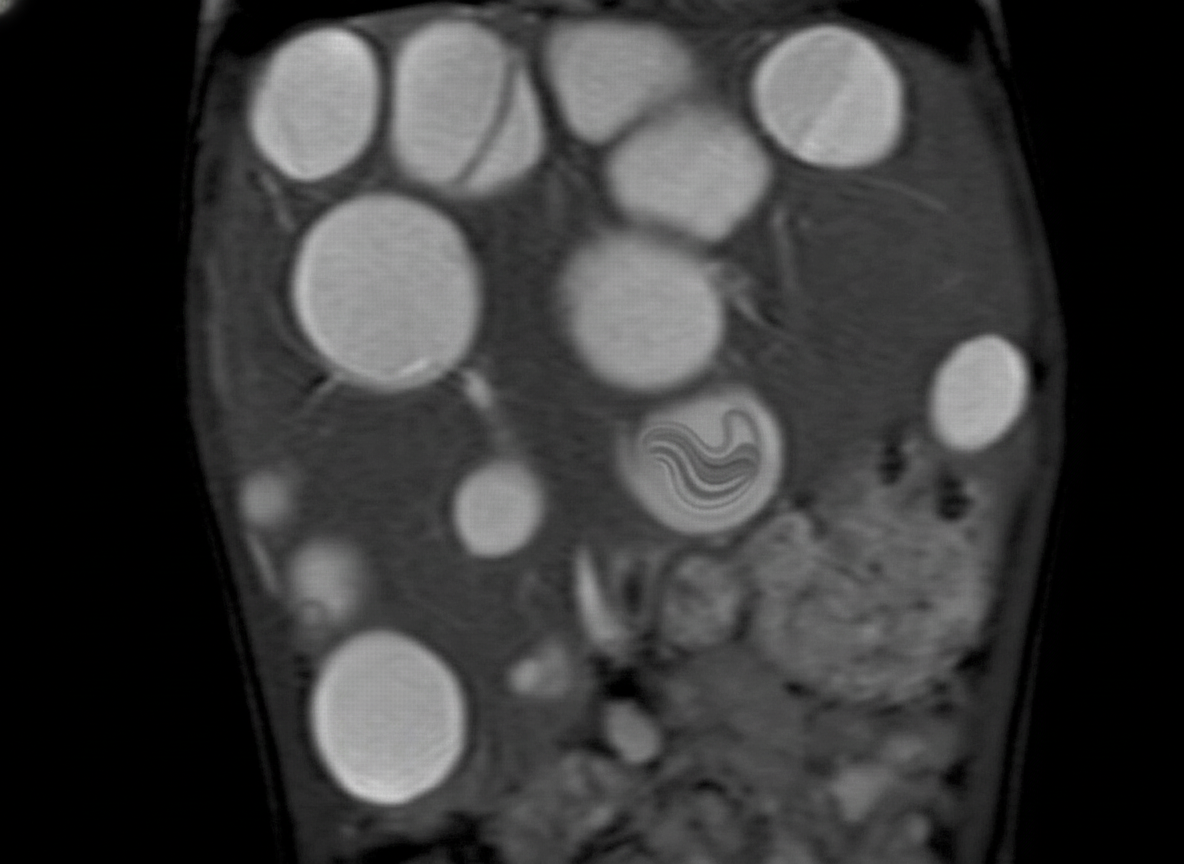

Comment on the diagnosis shown below?

Explanation: ***Drooping water lily sign*** - This is the **classic radiological appearance** of a **hydatid cyst** (echinococcosis) where the detached **inner endocyst membrane** floats on fluid like a water lily on water surface. - Also known as the **camalote sign**, it indicates **cyst rupture** or **membrane detachment** and is pathognomonic for echinococcal cysts on imaging. *Horse shoe kidney* - This refers to a **congenital renal fusion anomaly** where both kidneys are connected at the lower poles, creating a horseshoe shape. - Typically shows **bilateral renal masses** connected across the midline with **malrotation** of the collecting systems. *Flower Vase kidney* - This describes the appearance of **chronic pyelonephritis** where there is **cortical scarring** overlying **dilated calyces**. - The kidney shows a **club-shaped calyceal dilatation** with overlying cortical thinning, resembling a flower vase shape. *Duplication of kidney* - This refers to **complete or incomplete duplication** of the **collecting system** with two separate ureters or a bifid ureter. - Shows **two distinct pelvicalyceal systems** within the same kidney, often with the upper pole ureter inserting ectopically.